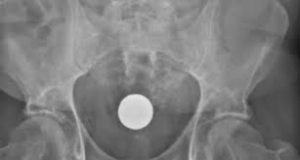

O homem chegou ao hospital com batimentos cardíacos acelerados e respiração ofegante. Após exames, a equipe identificou a perfuração intestinal e realizou uma laparotomia de emergência — cirurgia para abertura da cavidade abdominal. O procedimento permitiu a retirada dos ovos e a limpeza da área afetada, evitando que a infecção se espalhasse.